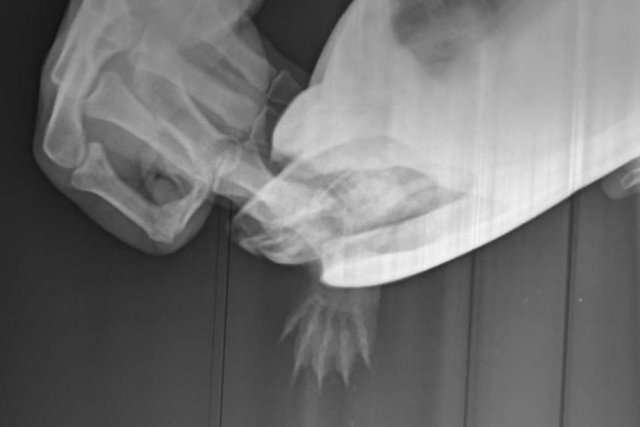

Алексей Alex-Raduga Ваше имя: Алексей Локация: Россия, МО, Серпуховский район Опубликовано: 29 марта 2024 Автор Опубликовано: 29 марта 2024 (изменено) @moth Есть рентген, она сначала долго пыталась вытащить лапку, снимок получился только одна кисть, потом снимала через панцирь. Вот оба снимка. Вообще она лапкой шевелит, даже плавала ей шевелила, кожа немного содрана только с пальцев. Рентген Тотоши не записали мне на флешку, я позвонил - должны прислать на E-mail, жду. Изменено 29 марта 2024 пользователем Алексей Alex-Raduga

Консультанты moth Ваше имя: Мария Локация: Москва Опубликовано: 30 марта 2024 Консультанты Опубликовано: 30 марта 2024 @Алексей Alex-Raduga Мария сказала перелома нет, ничего специального делать не нужно.